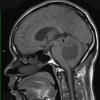

NEOPLASMS (MESENCHYMAL, NON-MENINGOTHELIAL)

Hemangioblastoma (9)